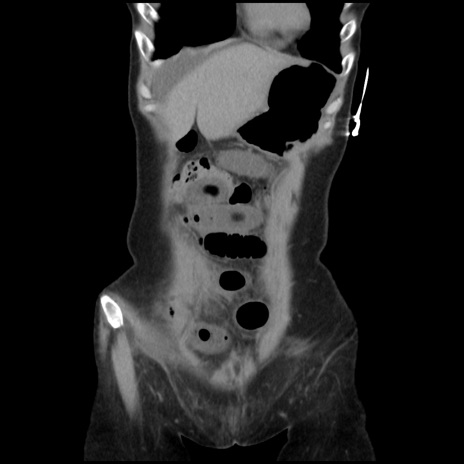

症例32(冠状断像)

【症例】40歳代 女性

【主訴】上腹部痛、嘔気・嘔吐

【現病歴】約9時間前頃から急に上腹部痛、嘔気、嘔吐が出現。改善しないため救急要請。

【既往歴】子宮頚癌(広汎子宮全摘術、放射線療法)、腸閉塞

【身体所見】腹部:平坦、軟、腸雑音亢進、上腹部を中心に腹部全体に圧痛あり。

【データ】WBC 8400、CRP 0.03